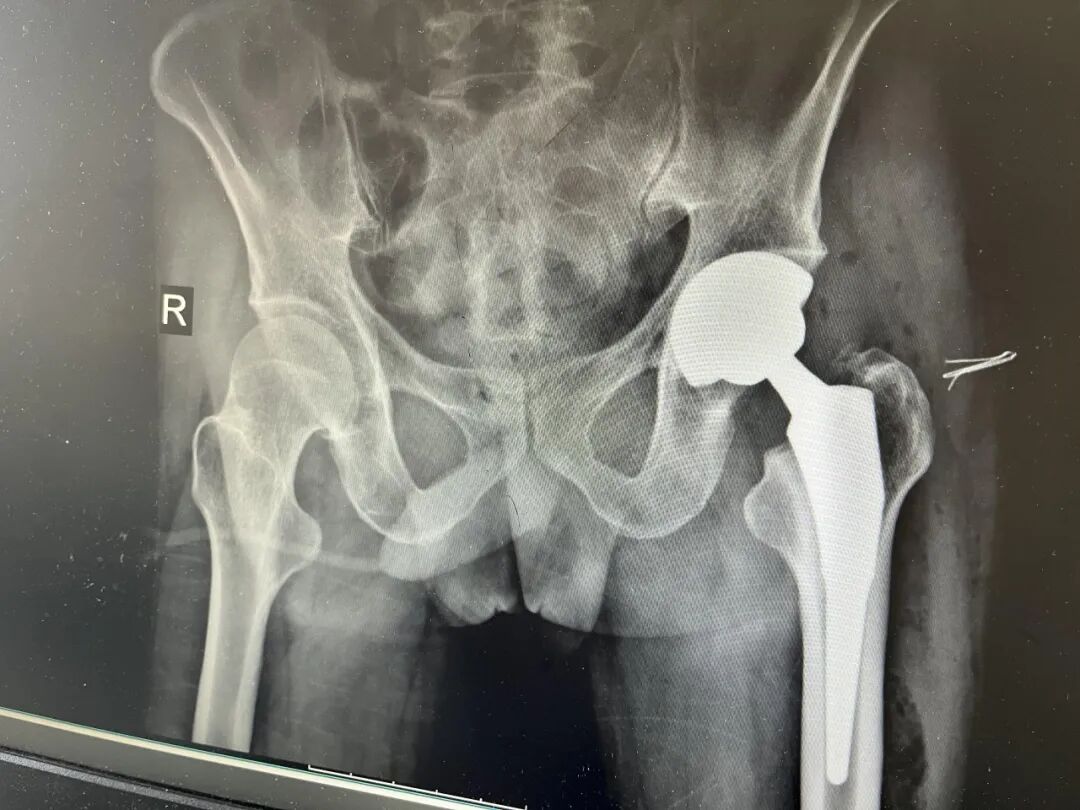

经过周密准备,王金台主任团队为患者顺利全髋关节置换术。手术顺利。术后第2天,患者在助行器协助下可以下床行走。“我没想到还能站起来走路,”患者激动地说,“这是我人生的新开始。”

术后X线

王金台主任表示,此次治疗的成功,不仅在于技术的突破,更在于我们对“整体疗愈”的坚持——它超越了单一的手术,体现了多学科协作与身心共治的现代医学理念。面对高风险且复杂的病例,我们深刻认识到,医疗的终极价值在于用技术修复健康,更在于以关怀重塑希望。此次经验,标志着八医在复杂关节置换与综合诊疗领域迈上了新台阶。